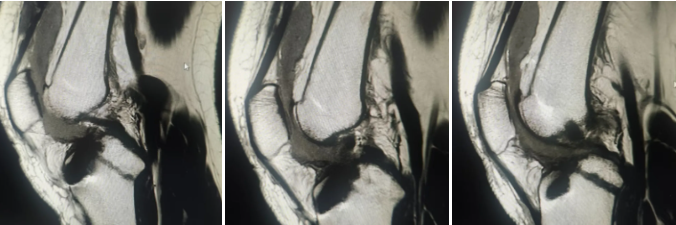

QQ截图20251015084032

术后复查膝关节MRI检查